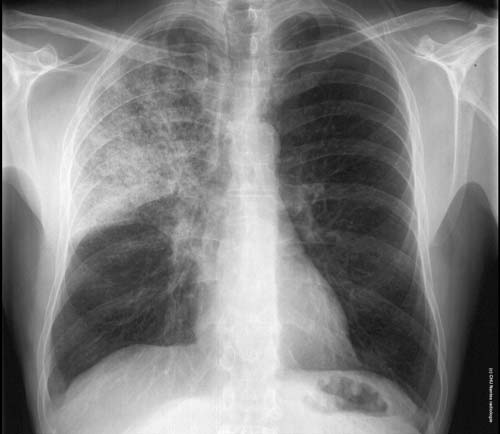

Syndrome interstitiel en rayon de miel